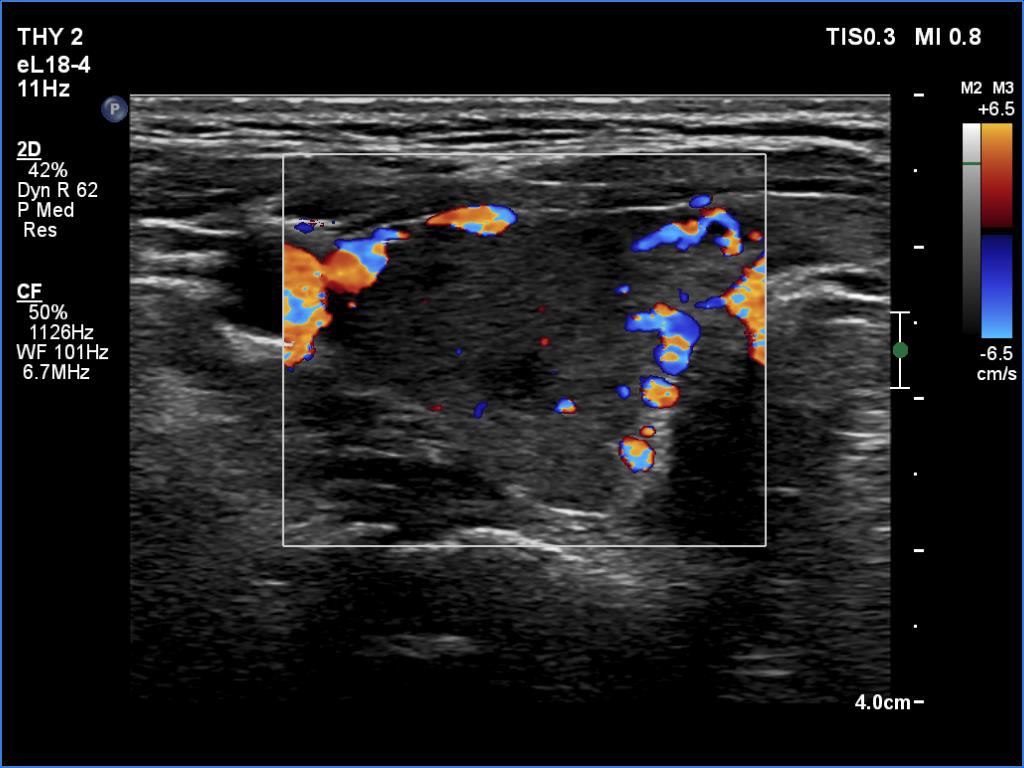

Right lobe, color Doppler mode

Left lobe, color Doppler mode

This is the typical course of a Graves' hyperthyroidism which does not relapse within a year. As the hormone result improves, both the size of the initially enlarged goiter and the degree of hypoechogenicity decrease.